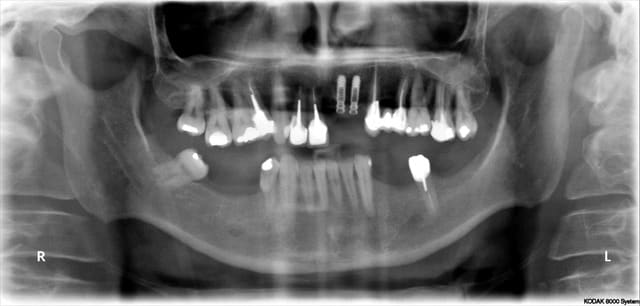

fini pour 2012 les 2 derniers

tu vois Pluton je ne passe toujours pas à la MCI pour ce genre de cas

d'un autre côté avec si peu de calage postérieur, je n'aurais pas fais non plus de mise en esthétique immédiate...;-)